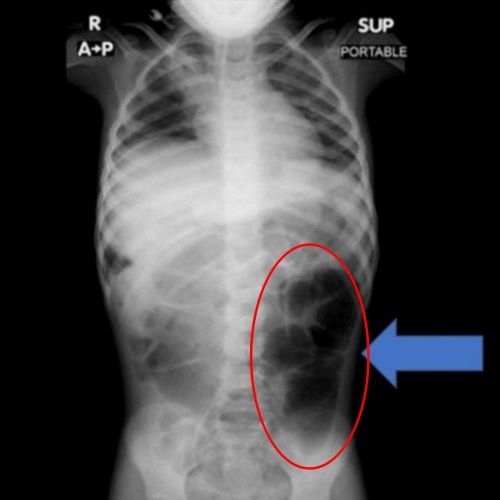

검사 결과 A양의 위 내부에서는 비정상적으로 큰 이물질이 발견됐으며, 의료진은 수술을 통해 이를 제거했다. 해당 이물질은 다량의 머리카락이 엉켜 형성된 덩어리로, 위에 머무는 데 그치지 않고 소장의 일부까지 길게 이어진 상태였던 것으로 확인됐다.

라푼젤 증후군은 머리카락을 뽑아 먹는 습관(발모식증·모발섭식증)으로 인해 위 안에 머리카락 덩어리가 생기고, 이 덩어리가 소장까지 길게 이어지는 매우 드문 질환이다.

주로 청소년과 젊은 여성에게서 나타나며, 불안·강박·스트레스 등 심리적 요인과 동반되는 경우가 많다. 주요 증상으로는 복통·복부 팽만을 비롯해 구토·소화불량·체중 감소·식욕 부진 등의 증상이 일어나며, 심하면 장 폐색·출혈·천공까지 나타나게 된다.